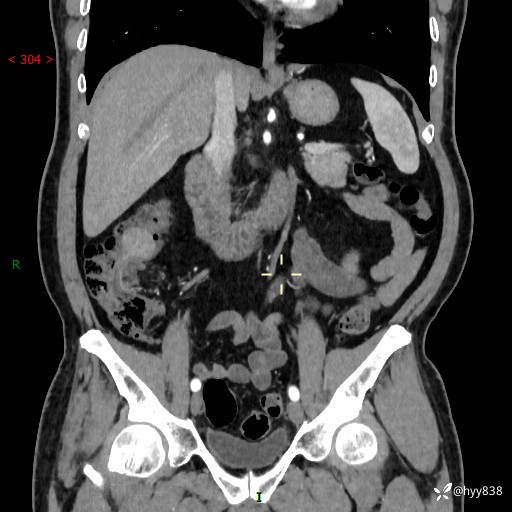

腹部CT增强扫描(外院CT平扫)

两期CT值:75hu 82hu